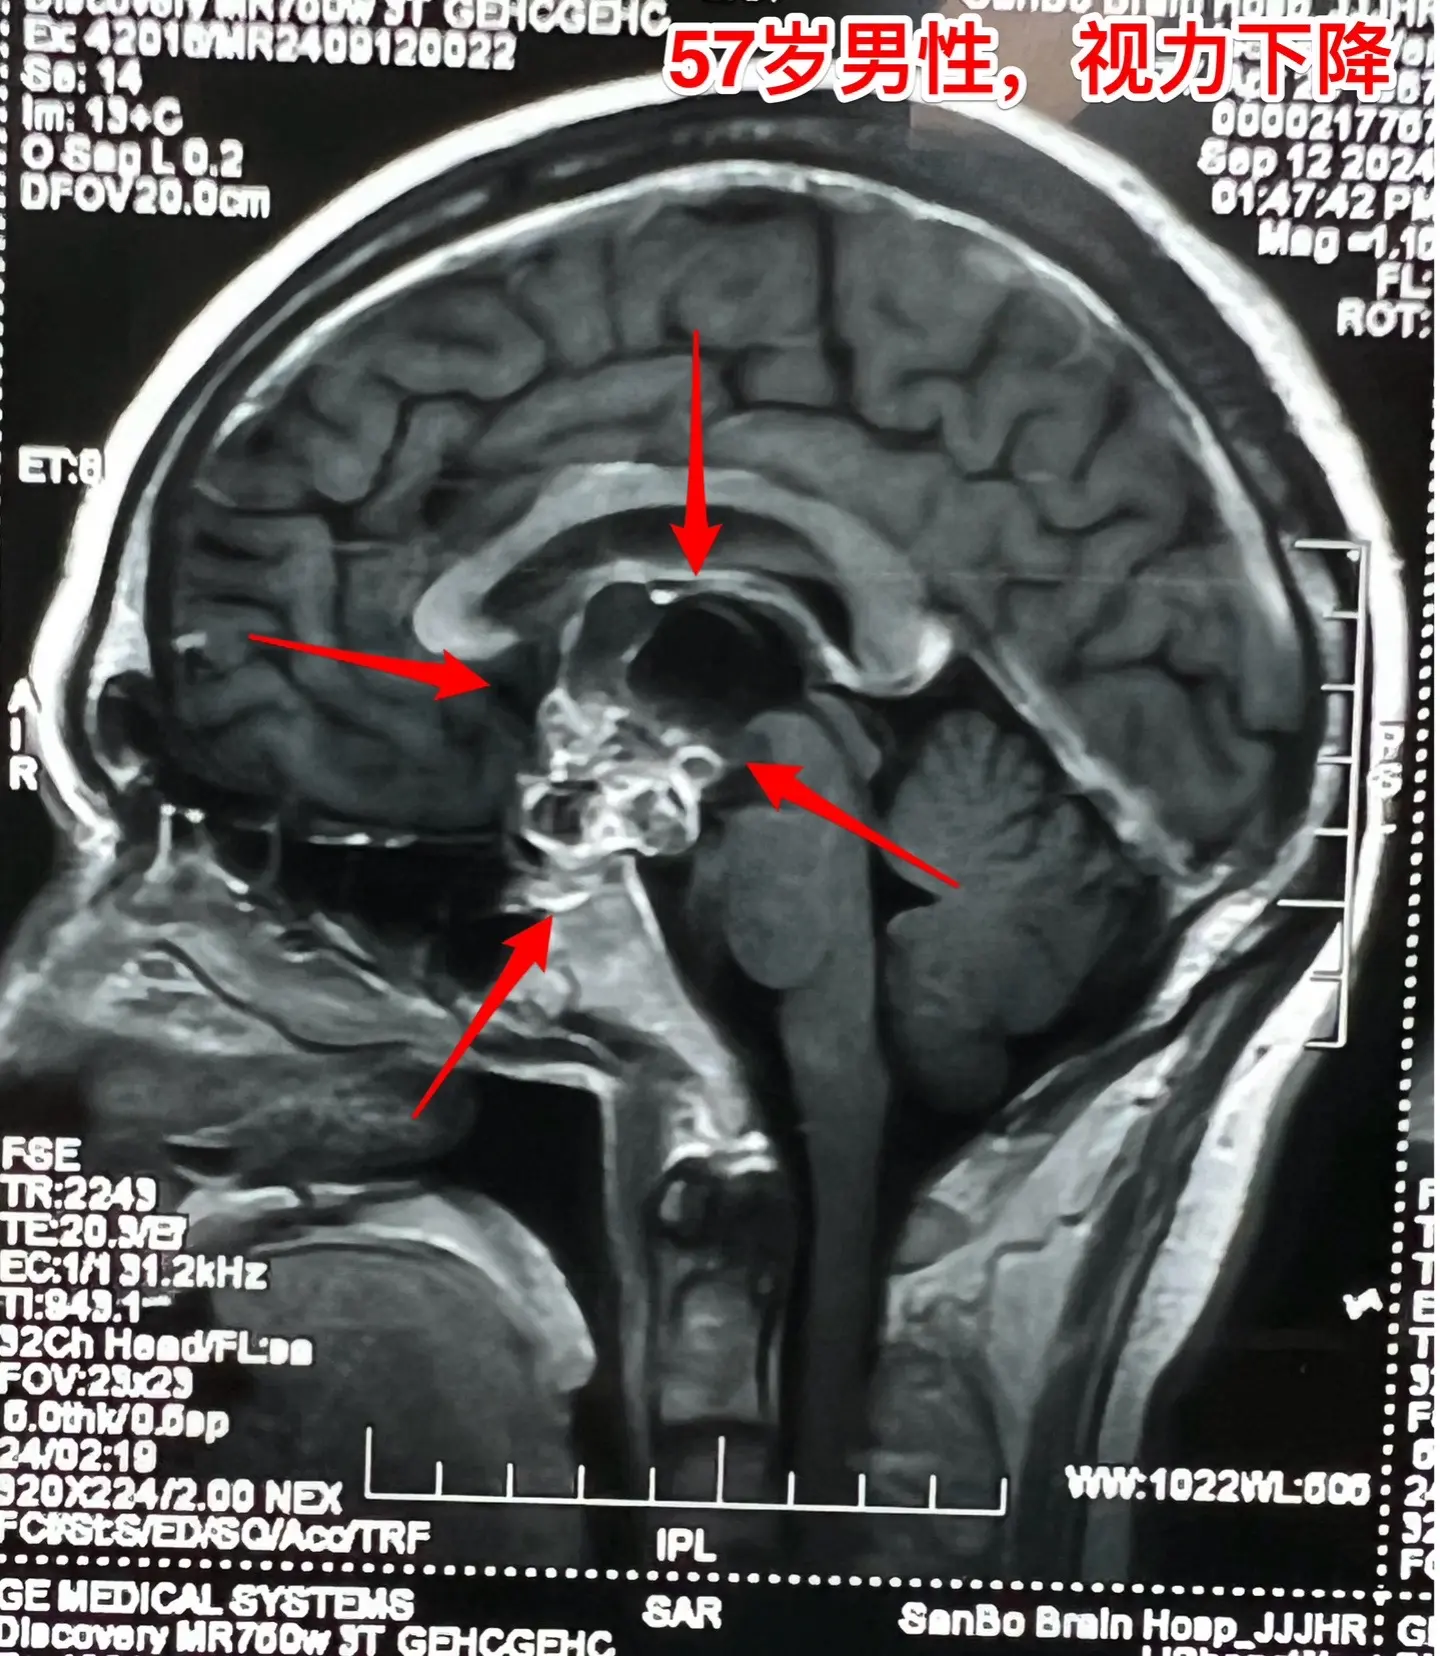

57岁男性,颅咽管瘤导致视力下降。病人因视力下降、消瘦到外院检查发现颅咽管瘤。如图所示,肿瘤体积比较大,有大量的钙化斑,是典型的造釉性颅咽管瘤。2024.9.20在我院行开颅手术,将颅咽管瘤完全切除。手术后患者视力明显改善了。十一前已经出院了,出院前体重有增长。